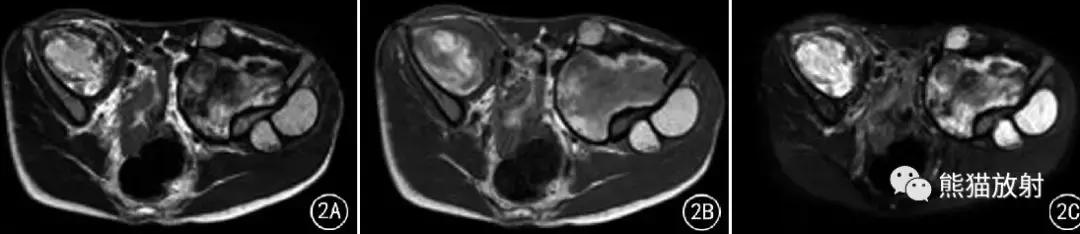

图2 男21岁。右侧髂前窝及左侧髂周围肌间型假肿瘤(血肿) 。右侧髂前方、左侧髂周围软组织块,左髂骨翼局部骨质侵蚀性吸收,邻近组织受压移位; T2WI(A) 、T1WI(B) 、SPAIR(C) 均呈高、低混杂信号。